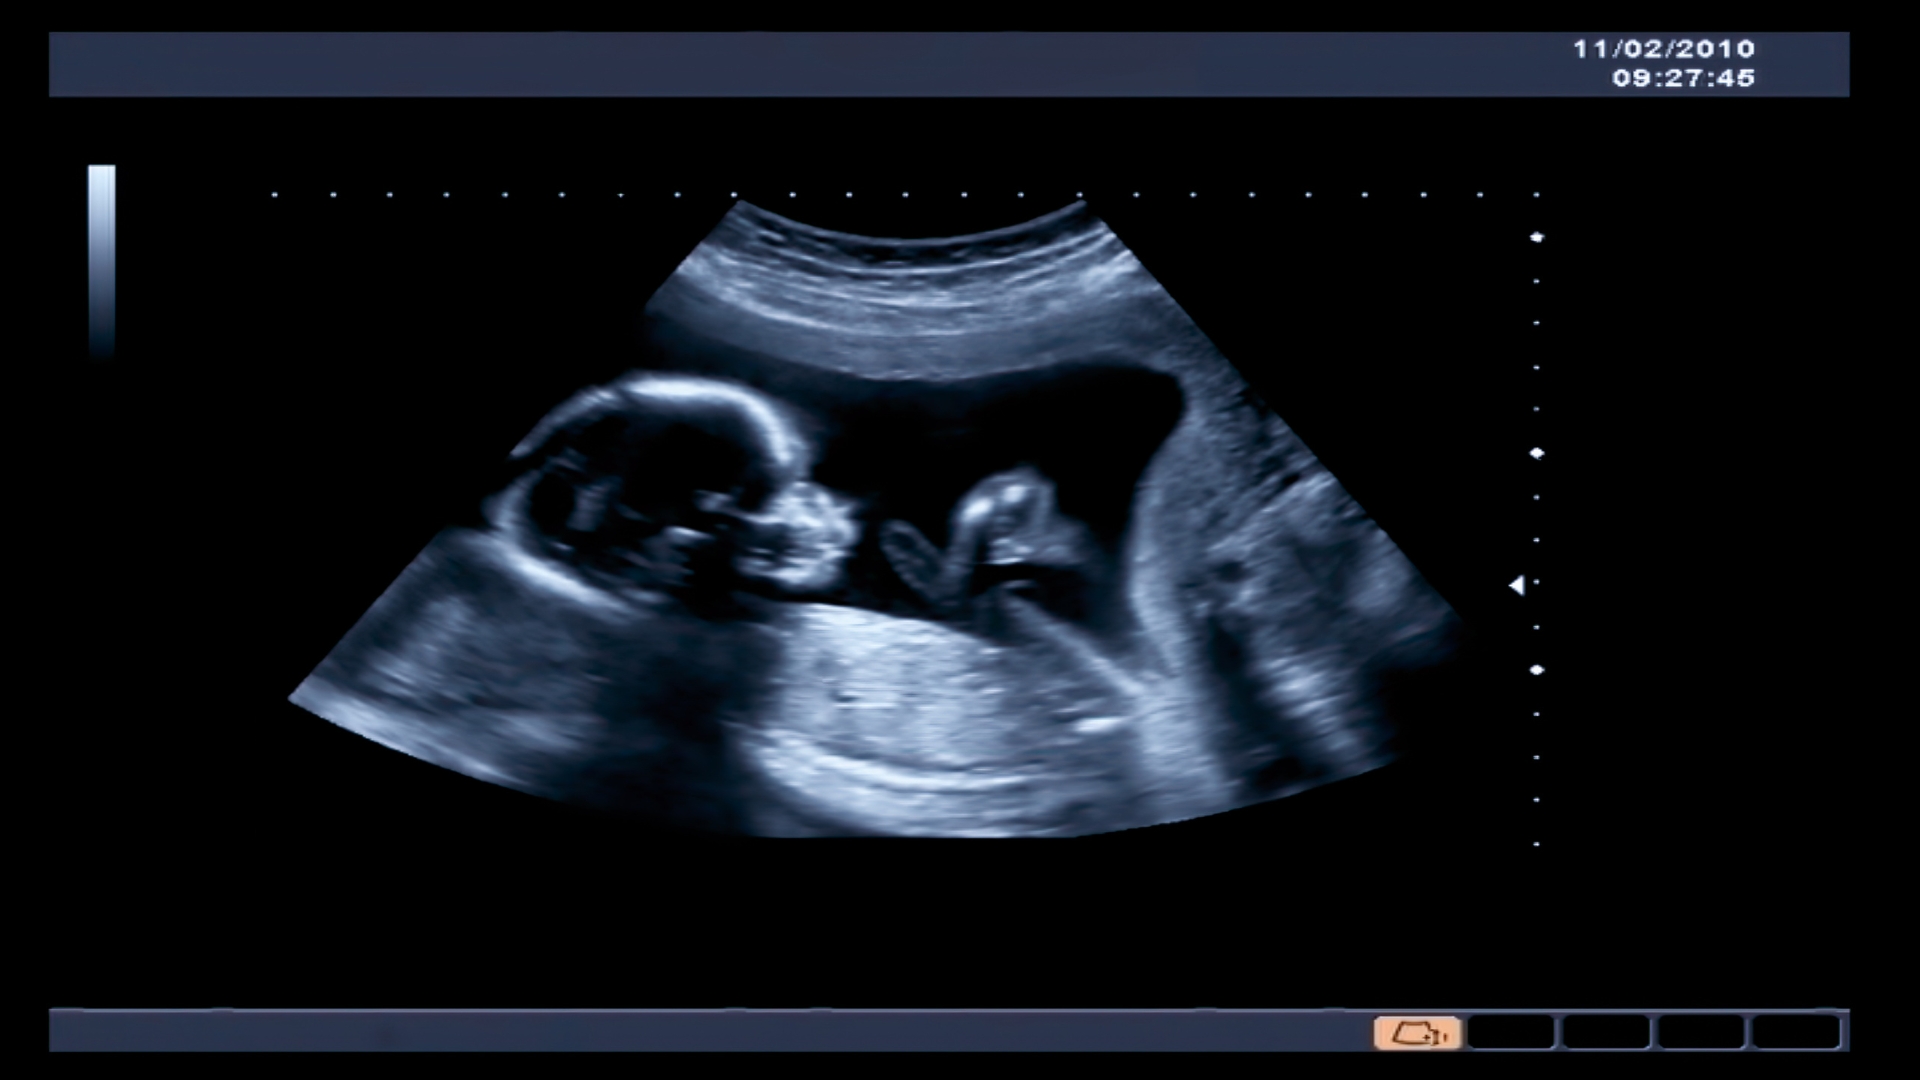

Nước ối cạn bao nhiêu thì phải mổ là mối quan tâm của nhiều mẹ bầu khi bước vào những tuần cuối thai kỳ. Thực tế, bác sĩ không chỉ dựa vào cảm giác bụng nhỏ hay thai máy yếu để chỉ định mổ, mà chủ yếu dựa trên chỉ số nước ối thông qua siêu âm - gọi là chỉ số AFI (Amniotic Fluid Index).

Theo hướng dẫn của nhiều tổ chức sản khoa, khi chỉ số AFI dưới 5 cm được xem là thiểu ối nặng. Tuy nhiên, bác sĩ cũng cần kết hợp các yếu tố khác trước khi quyết định mổ, bao gồm:

Siêu âm định kỳ là biện pháp quan trọng giúp theo dõi lượng nước ối và can thiệp kịp thời khi cần thiết.

Cách tốt nhất để phát hiện là đi siêu âm định kỳ từ tuần 28 trở đi. Đặc biệt, nếu mẹ thuộc nhóm nguy cơ (tăng huyết áp, tiểu đường, thai quá ngày…), cần theo dõi kỹ hơn mỗi tuần ở giai đoạn cuối. Phát hiện sớm sẽ giúp mẹ có thời gian điều trị bảo tồn, tránh phải mổ gấp hoặc đối mặt biến chứng.